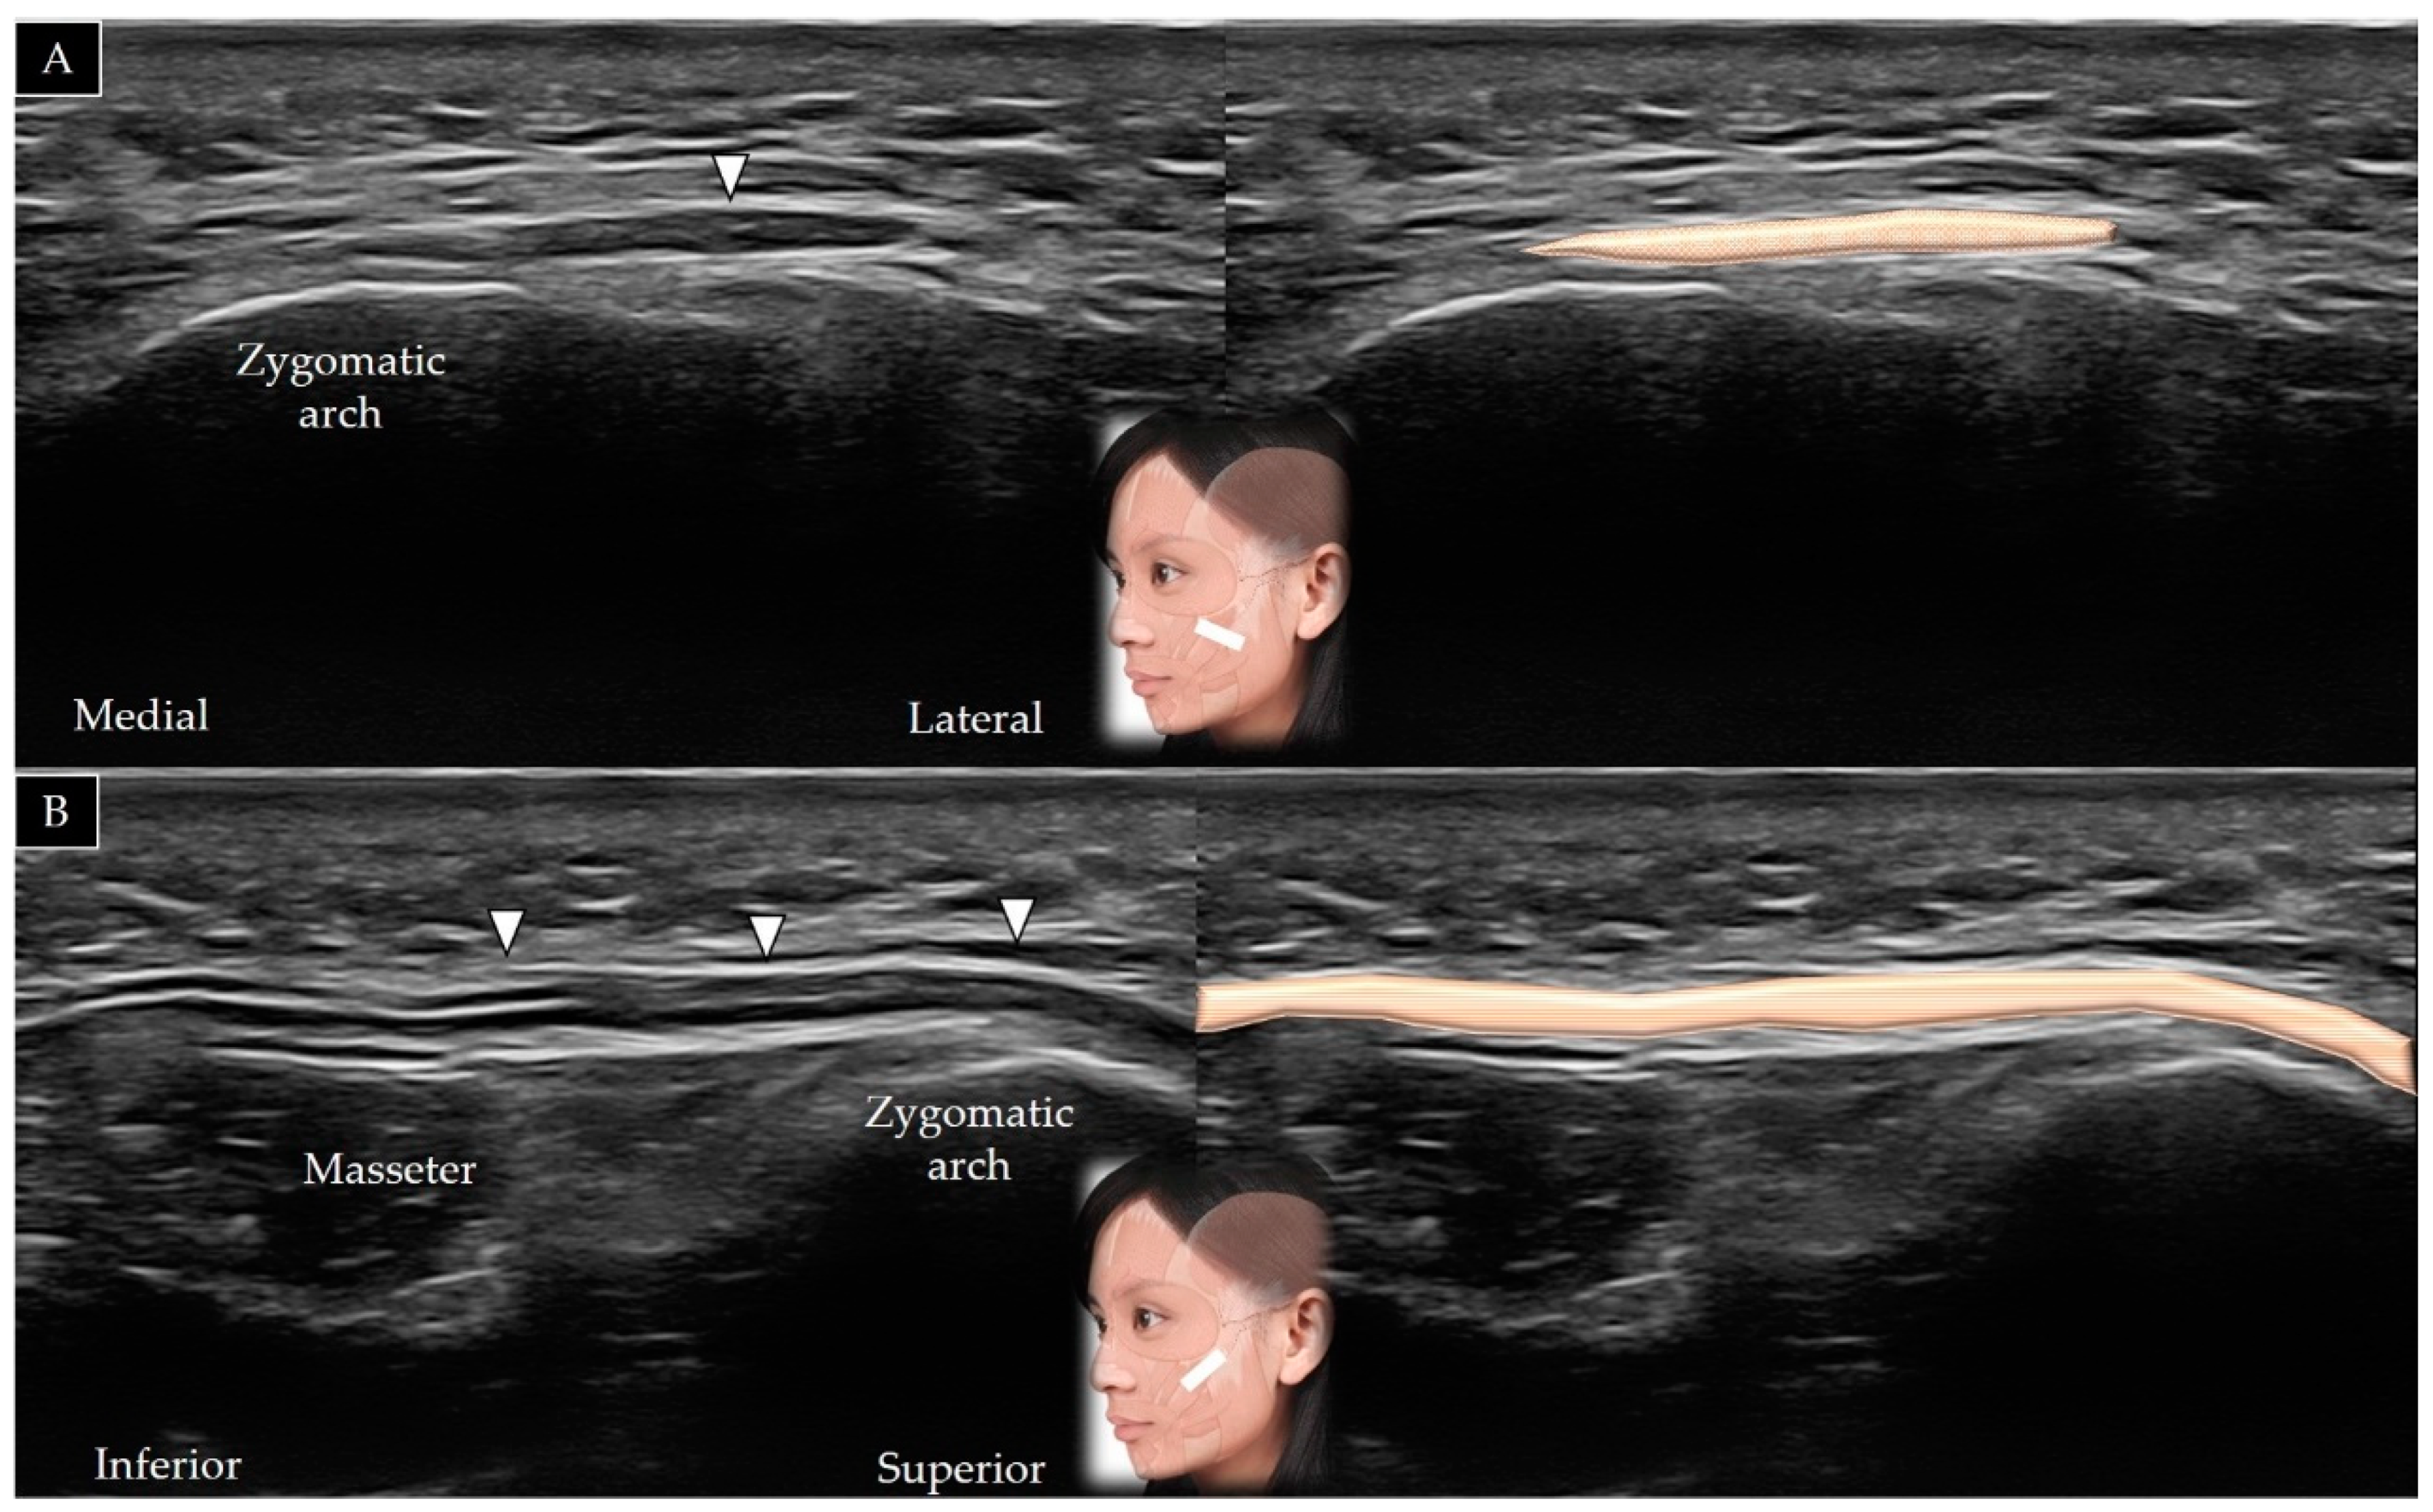

4.7. Masseter

4.7.2. Scanning Technique

| Masseter | Zygomatic arch | Mandibular ramus and angle | In the horizontal plane along the zygomatic arch, then moved caudally (short axis view) |